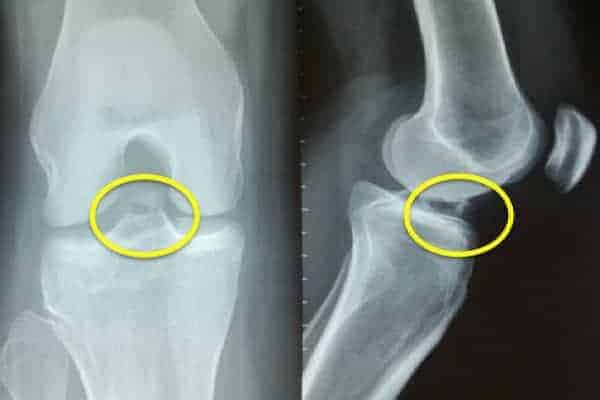

Lorsqu’un patient avec une avulsion des épines tibiales est initialement vu pour une évaluation en clinique, le médecin demande des radiographies. L’avulsion des épines tibiales se voit sur une radiographie standard, en cas de doute un scanner permet de confirmer le diagnostic. Le médecin peut également ordonner un examen d’imagerie par résonance magnétique (IRM) pour évaluer l’état du LCA et vérifier la présence de lésions à d’autres ligaments du genou, du ménisque ou du cartilage articulaire.

Radiographie montrant un arrachement déplacé des épines tibiales